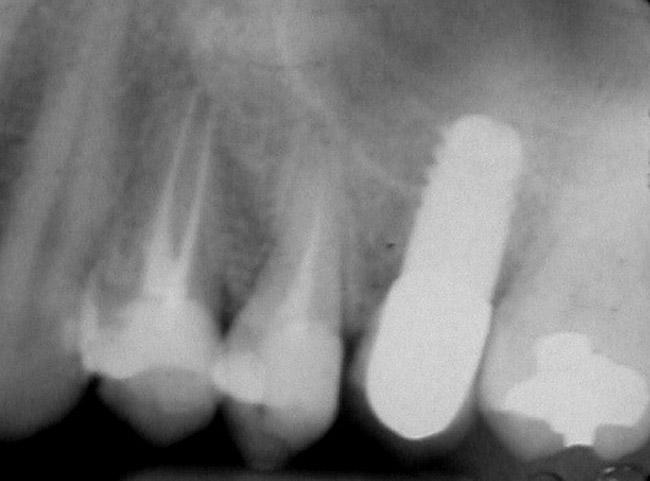

A 45-year-old female was referred for implant placement and prosthetic treatment in the area of tooth No. 24. The tooth had been extracted 4 years prior; the patient did not wear any denture thereafter. The radiograph revealed adequate bone height and a 5-mm to 6-mm ridge at the crest (Figure 2). It was decided to place a 11.5 mm in length, 3.75 mm in diameter Tapered Screw-Vent® implant (Zimmer Dental, www.zimmerdental.com) using the alveolar remodeling technique in the area of tooth No. 24.

Figure 2  Preoperative view of the area around tooth No. 24. On the left, a previously placed implant abutment is visible.

Figure 2